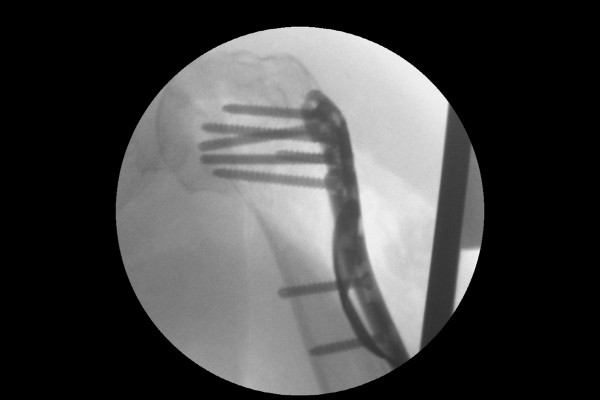

실시간 X-RAY인 C-ARM을 이용하여 실시간으로 확인하며 임시 고정한 후

b72968fc2915dd5bd436116d60cd6556_1767926771_4549.jpg

강하게 스크류 금속판 고정을 합니다.